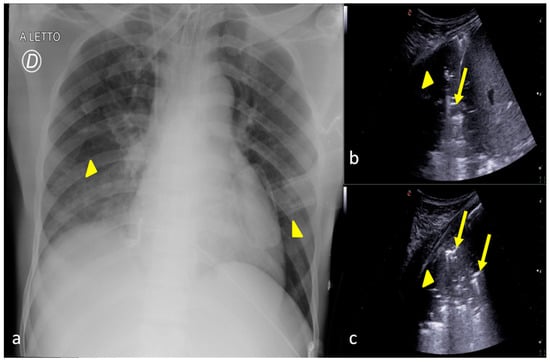

3. Confirming or Excluding Pneumothorax and Monitoring its Evolution

- Thachuthara-George, J. Pneumothorax in patients with respiratory failure in ICU. J. Thorac. Dis. 2021, 13, 5195–5204. [Google Scholar] [CrossRef]

| Pneumothorax | Portable chest radiography has a sensitivity of 19.8–31.8% and specificity of 99.3–100%. | The overall sensitivity and specificity of US in the detection of pneumothorax are 78.6–100% and 96.5–100%. |